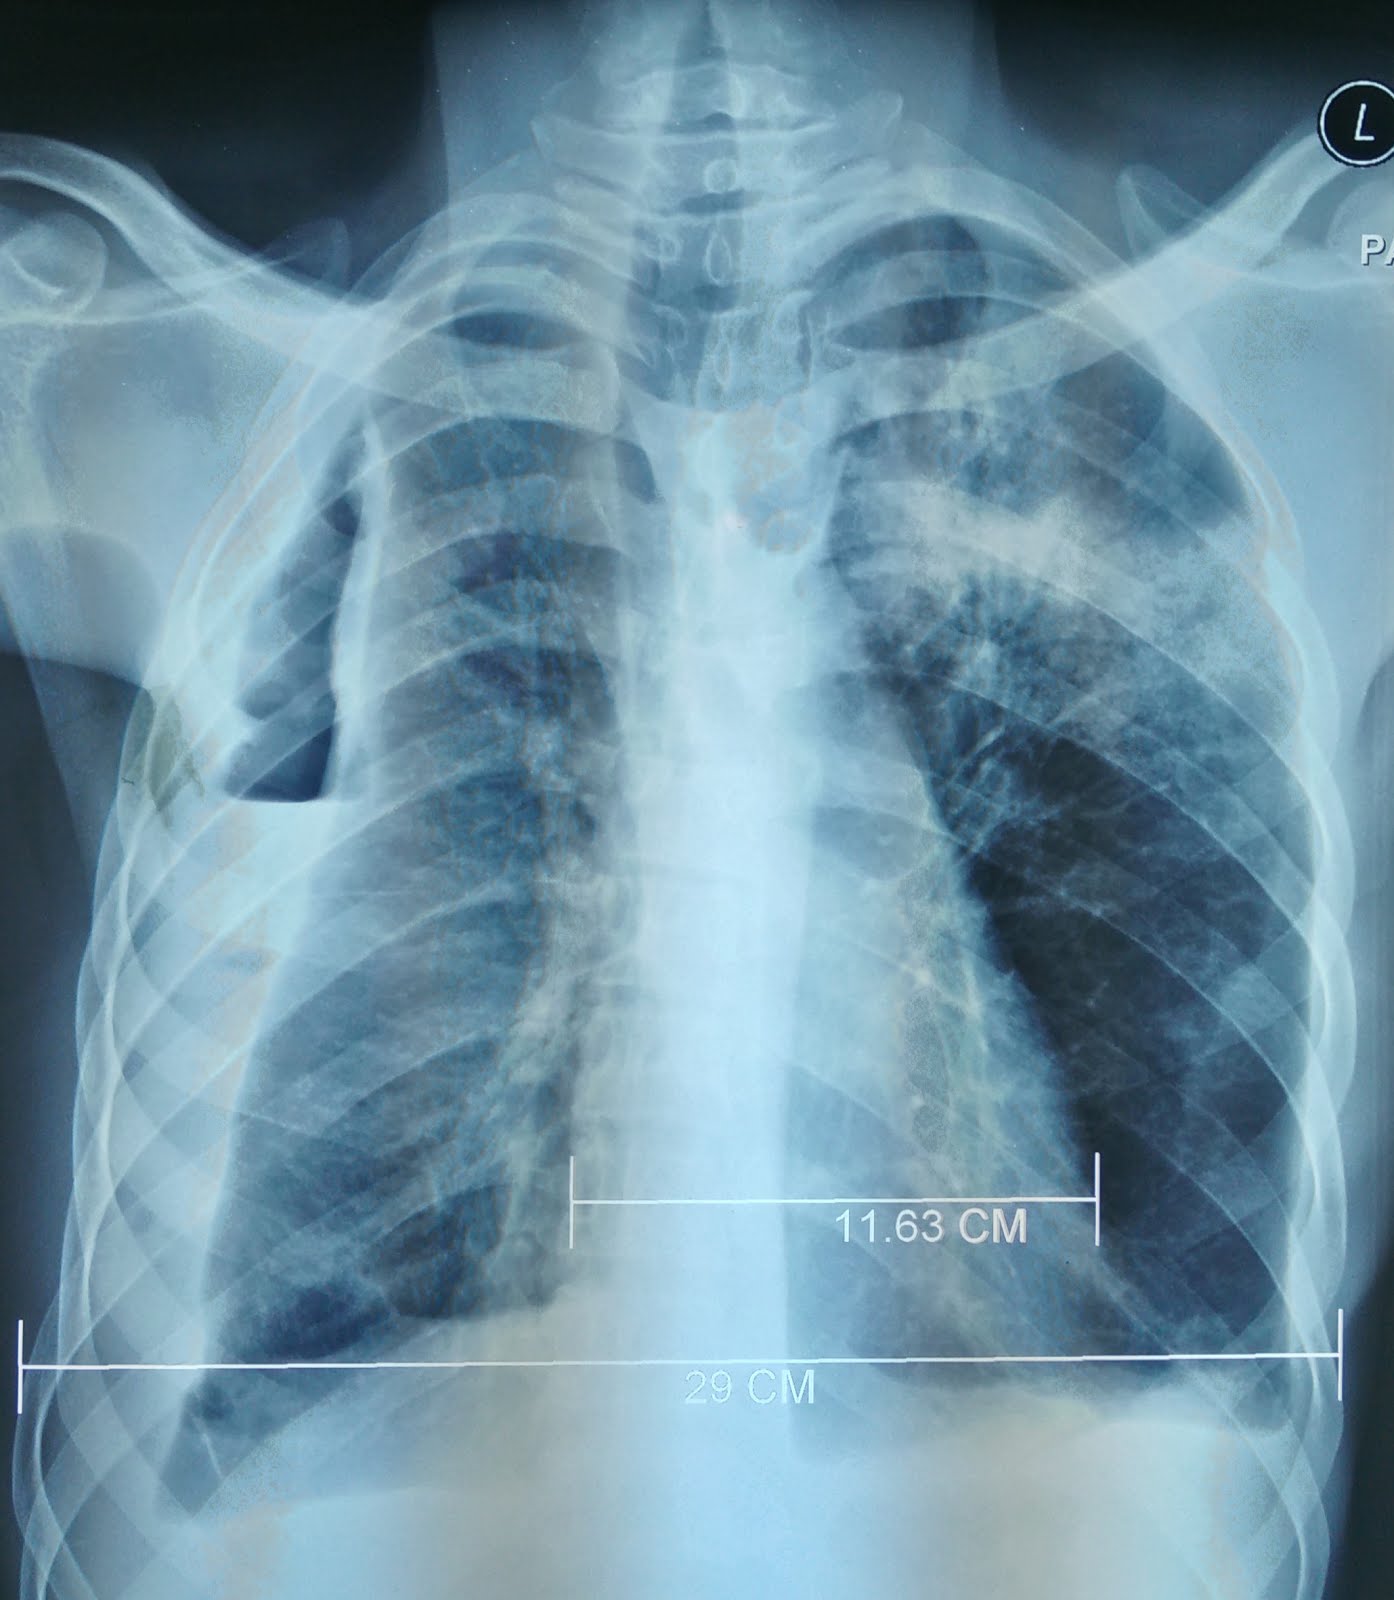

Treating Chest Trauma